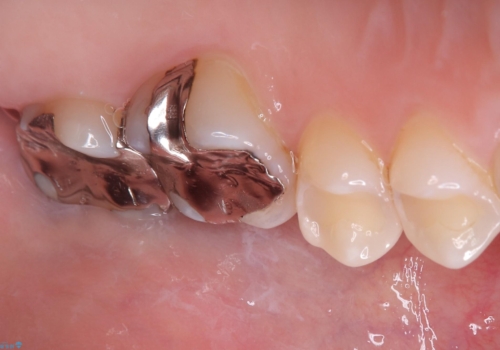

- 主訴:銀の詰め物を白くしたい

保険メタルインレーの入っている歯に虫歯が認められたため、セラミッククラウンでのやり替えとなりました。

左上6の近心にカリエスを認め、残存歯質と破折リスクの観点からセラミッククラウンでのやり替えとなりました。